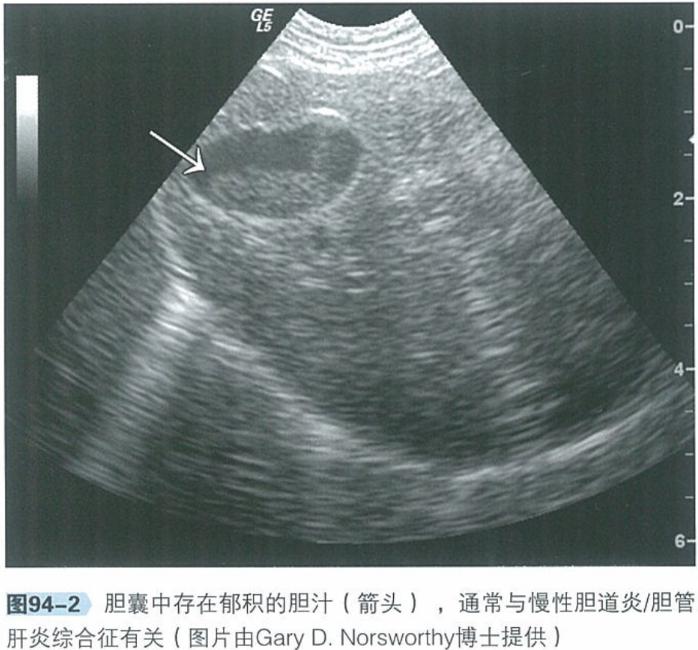

b.腹部超声:腹部超声是检查肝脏、胆管系统及胰腺实质结构极为有用的工具。肝脏回声通常正常,胆管及胆囊可见异常,包括胆总管、胆囊或肝内胆管扩张、部分或完全阻塞,胆汁淤积。

10.5 治疗